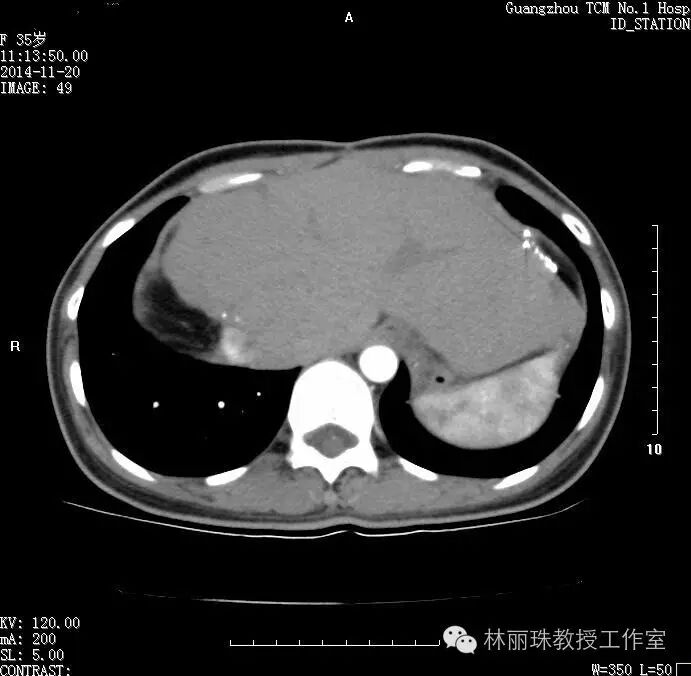

20141120日,治疗后2年,CT示患者肝内无明显病灶